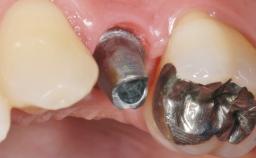

Early Placement of an Implant in a Maxillary Right Central Incisor Site

This 41-year-old female patient was referred to the clinic for the replacement of the right central incisor, since the tooth had developed a root fracture in the long axis that made extraction necessary. The healthy, non-smoking patient was first seen with the tooth still in place. A detailed Esthetic Risk Assessment was performed.The patient was worried about her dental esthetics and had high expectations for a successful treatment outcome from an esthetic point of view. The patient had a medium lip line that displayed parts of the gingiva in the anterior maxilla upon smile.

Abutment Type Customized

Prosthesis Type FDP

Loading Protocol Conventional or early

Retention Cemented, with prosthesis margin < 3mm submucosal Cemented, with prosthesis margin < 3mm submucosal